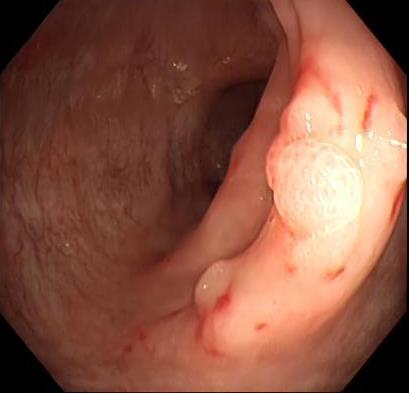

• 获得性免疫缺陷综合征合并马尔尼菲篮状菌导致肠道感染的内镜下表现(附6例报告)

2026, 32(3):84-88. DOI: 10.12235/E20250461

摘要 (32) HTML (27) PDF 3.50 M (26) 评论 (0) 收藏

摘要:目的 探讨获得性免疫缺陷综合征(AIDS)合并马尔尼菲篮状菌(TM)感染导致肠道感染的内镜下特征。方法 回顾性分析2022年11月-2024年10月于该院确诊为AIDS合并TM感染导致肠道感染的6例患者的临床资料。包括:临床症状、实验室检查、影像学检查、内镜检查和病理检查等。结果 6例患者中,男5例,女1例;发病年龄26~67岁;AIDS合并TM感染导致肠道感染患者的临床表现为:腹泻、腹痛、腹胀和恶心呕吐。其中,2例有消化道出血表现。实验室检查:6例患者外周血白细胞计数为(1.37~4.49)×109/L,血红蛋白计数为(67~99)g/L;CD4+T淋巴细胞为(1~52)个/μL,CD8+ T淋巴细胞为(61~321)个/μL,CD4+T淋巴细胞/CD8+T淋巴细胞比值为(0.01~0.18)。6例患者均行HIV RNA检测。其中,5例HIV RNA阳性。血培养:可见丝状真菌,报告显示为TM。影像学检查:6例患者CT结果可见肠系膜及腹膜后多发淋巴结肿大。内镜检查:6例患者内镜下均可见肠道病变。其中,十二指肠糜烂溃疡2例,结肠多发糜烂溃疡4例。病理检查:6例患者幽门螺杆菌(Hp)结果均为阴性,黏膜下可见成簇的小球形真菌孢子,符合TM感染;特殊染色:PAS(+),六胺银染色(+)。结论 当AIDS晚期患者出现消化道症状时,应警惕TM感染,病变部位常见于全结肠和直肠,亦可累及十二指肠,内镜下表现多为溃疡、糜烂和隆起性病变,形态表现无特异性;及时行胃肠镜检查、病理活检、特殊染色和免疫组化是确诊的关键。